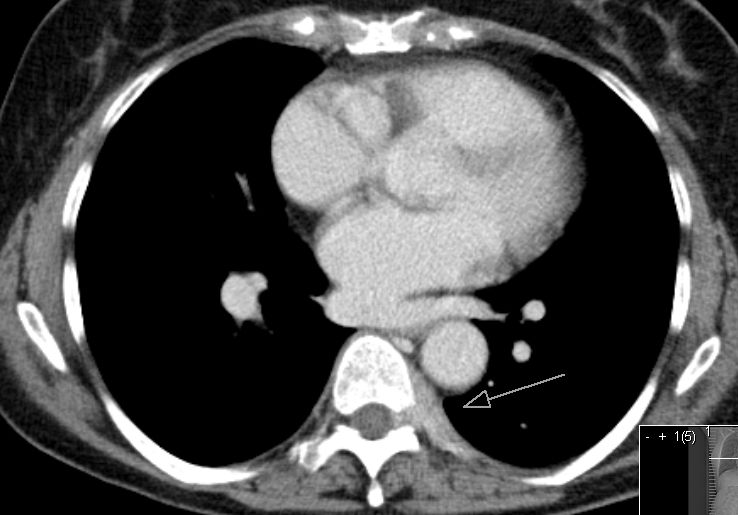

60-jährige Frau mit metastasierten Mammakarzinom. Jetzt

segmentförmige Schmerzen der linken Thoraxwand. das CT zeigt einen diskreten

Weichteiltumor mit Infiltration des Neuroforamens.![]() | |||||||||